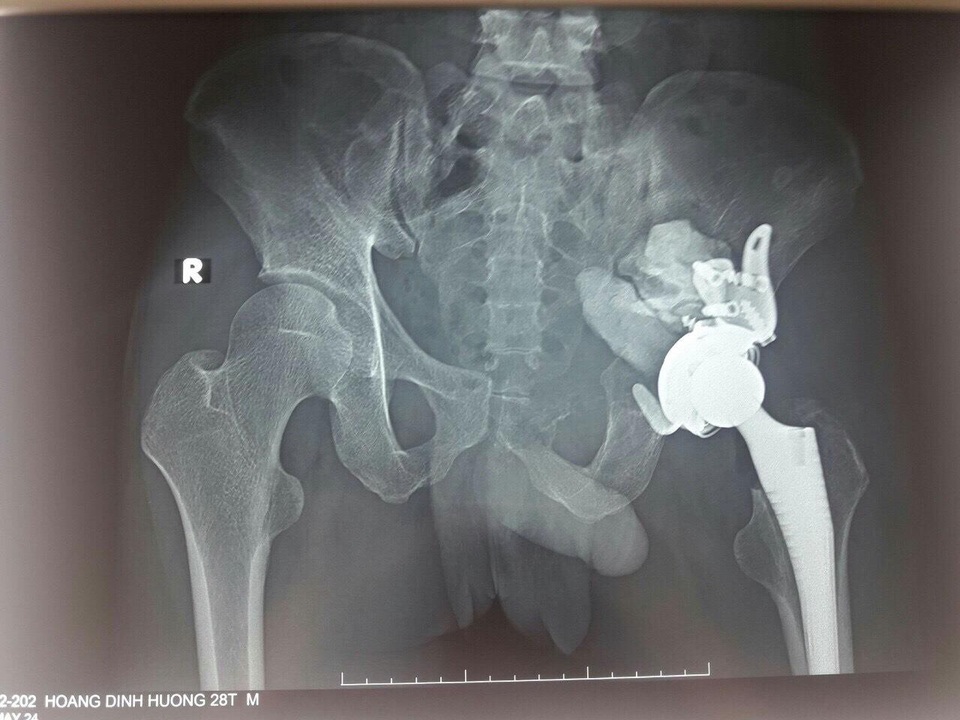

Tại BV K, các bác sĩ phát hiện bệnh nhân có một khối u ở vùng ổ cối xương chậu phá hủy gần hoàn toàn ổ cối và phát triển vào ổ bụng bệnh nhân tạo thành một khối đường kính khoảng 10cm. Kết quả sinh thiết chẩn đoán xác định u tế bào khổng lồ. Chỉ định phẫu thuật được đặt ra với mong muốn lấy bỏ khối u triệt để và tạo hình lại khớp háng để giúp cho bệnh nhân sinh hoạt vận động trở lại.

Các bác sĩ đánh giá, với vị trí phát triển của khối u từ phía ổ cối tương ứng với khu vực khuyết mẻ hông lớn và bé, nơi có dây thần kinh ngồi cùng với các bó mạch thần kinh mông trên và mông dưới đi qua, đây là khu vực hiểm yếu, có nguy cơ tai biến trong phẫu thuật rất cao. Hơn nữa, sự phá hủy hoàn toàn vùng đáy ổ cối làm cho khớp háng mất chức năng gần hoàn toàn, bệnh nhân không có khả năng tỳ đè chịu lực trên chân tổn thương, còn các động tác vận động không chịu lực của khớp háng.

Ca mổ đã trải qua rất căng thẳng, bệnh nhân phải nằm ngửa cho đường mổ bụng và nằm nghiêng cho đường mổ khớp háng. Đường mổ khớp háng phía ngoài rộng rãi để thăm dò ổ cối cánh chậu để cân nhắc phương án tạo hình lại khớp sau khi lấy bỏ khối u. Đường mở vào ổ bụng qua đường trắng giữa dưới rốn, kiểm soát bó mạch chậu trong, loại bỏ trọn vẹn khối u, làm sinh thiết tức thì đánh giá đảm bảo triệt để, cầm máu kỹ và sử dụng xi măng sinh học để phục hồi một phần khuyết xương cánh chậu và ổ cối.

Cùng với đó, các bác sĩ lựa chọn phương án tạo hình lại khớp háng với khớp háng nhân tạo có sử dụng rọ ổ cối để cố định ổ cối nhân tạo lên cả phần cánh chậu lành. Kíp phẫu thuật kiểm tra kỹ, đặt dẫn lưu và phục hồi giải phẫu của bao khớp và phần mềm. Sau 6 giờ đấu trí cam go, ca phẫu thuật đã diễn ra thành công, khối u được lấy bỏ triệt để, không có tai biến tổn thương thần kinh, khớp háng được phục hồi bằng khớp háng nhân tạo giúp cho bệnh nhân có thể tập luyện dần trở lại.